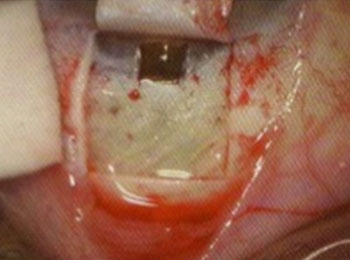

Chirurgie de la cataracte

L’intervention chirurgicale visant l’extraction de la cataracte se déroule dans un bloc opératoire stérile et à la fine pointe de la technologie...